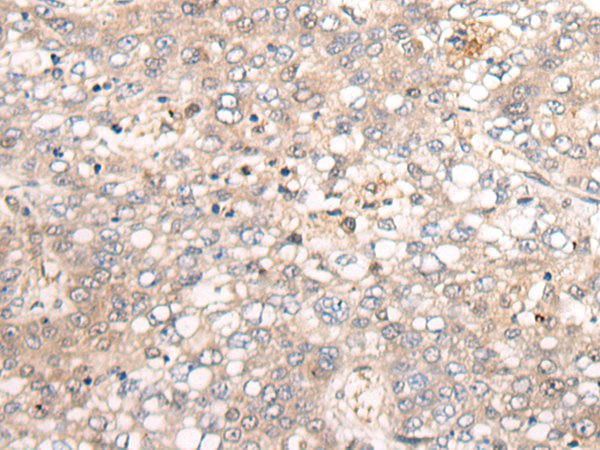

分类: 科研抗体货号: P05700别名: FH; FHC; LDLCQ2应用: IHC反应种属: Human, Mouse, Rat